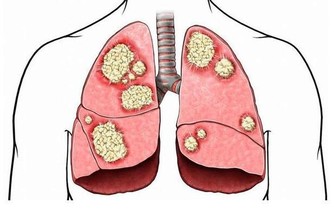

發生腦動脈硬化、血管脂質沉積等腦血管疾病時,會降低血腦屏障的通透性,導致腦組織缺血、缺氧,出現嗜睡。大腦長期缺氧還可能產生一系列的精神、神經狀。如記憶力下降、行為異常、個性改變等。

解決辦法:休息時適當放低頭部,能夠促進頭部的血液循環,這樣可以增加氧分,讓腦部能夠及時的補充氧氣,是最快最有效的方法之一。另外需要加強有氧運動,如散步、慢跑、深呼吸等。